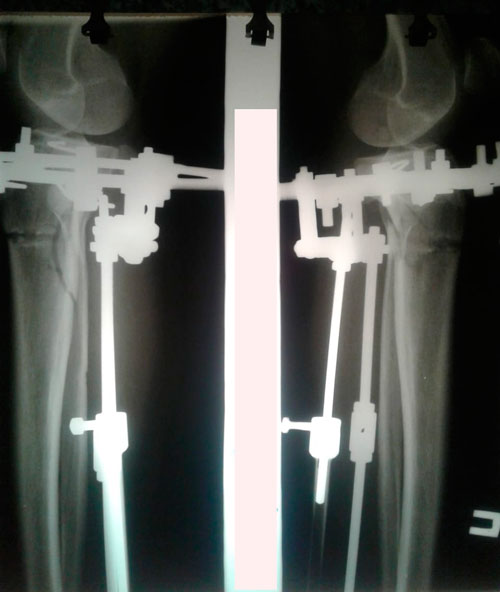

Исходник-43 года. Казахстан.

Дата операции - 08.01.2019г.

перед крутками.